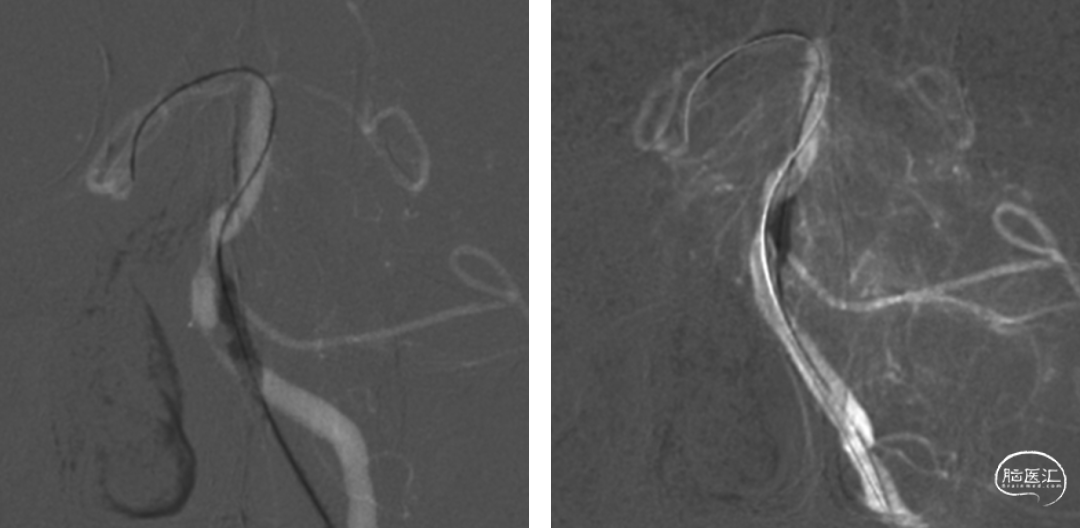

基底动脉中下段重度狭窄,串联病变;右椎动脉纤细,止于右侧小脑后下动脉。椎动脉造影双侧大脑后动脉未见显影,颈动脉造影可见双侧后交通动脉开放。

微导丝置于右侧小脑上动脉,导引Fastunnel®通过狭窄。

分别对近端狭窄及远端狭窄进行扩张。

扩张后造影,狭窄较前明显改善,右侧大脑后动脉显影。

沿球囊送入NeuroStellar® 4.5mm*30mm颅内支架一枚,定位准确后释放支架。

术后即刻造影支架位置良好,支架内管腔通畅,远端双侧大脑后动脉均可显影,残余狭窄率<10%,Vaso-CT可见支架打开良好。麻醉清醒后无新发神经功能缺损症状及体征。